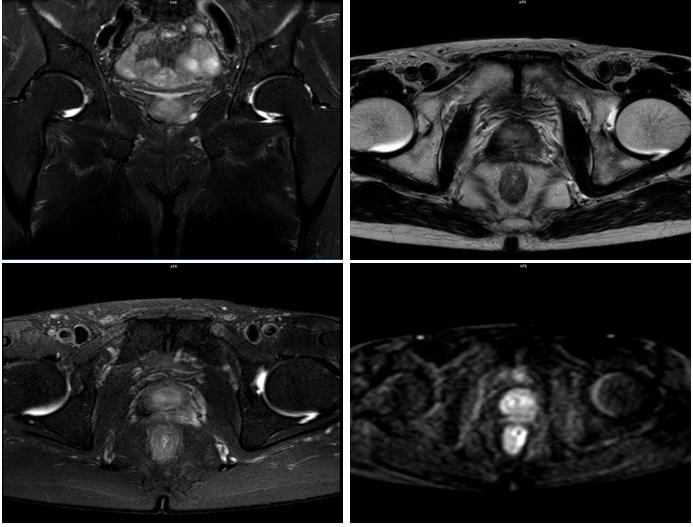

2020年5月12日,复查前列腺MRI+DWI示:前列腺信号欠均,DWI信号略高,外周带及中央带分界不清,盆腔未见明显肿大淋巴结。双侧精囊腺萎缩信号欠均。右侧耻骨联合见斑片状SPAIR高信号。

图4 患者起始醋酸阿比特龙治疗时,复查前列腺MRI+DWI状况

2020年5月13日,复查全身骨显像示:考虑为肿瘤骨转移,与上次检查比较右侧第8前肋为新增病灶,其余病灶数目较前减少。

图5 患者复查骨显像状况